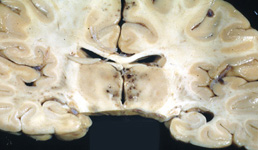

Question 5: A 56 year old man died of gastric carcinoma. The autopsy revealed pathological changes in the brain shown below. The changes are due to:

Incorrect. The pathology (petechiae in the mammillary bodies and around the 3rd ventricle) represents acute Wernicke-Korsakoff syndrome which is caused by Vitamin B1 deficiency.

Correct. The pathology (petechiae in the mammillary bodies and around the 3rd ventricle) represents acute Wernicke-Korsakoff syndrome which is caused by Vitamin B1 deficiency.